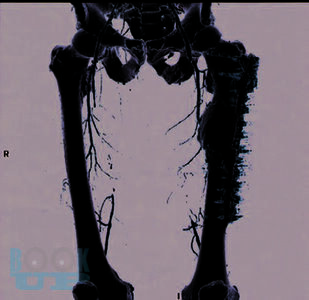

В монографии показаны ближайшие и отдаленные результаты бедренно-подколенного шунтирования в зависимости от вида трансплантата; представлена технология медицинской реабилитации пациентов. Особое внимание уделено послеоперационным осложнениям и методике лечения больных с окклюзионным поражением бедренно-подколенного сегмента.